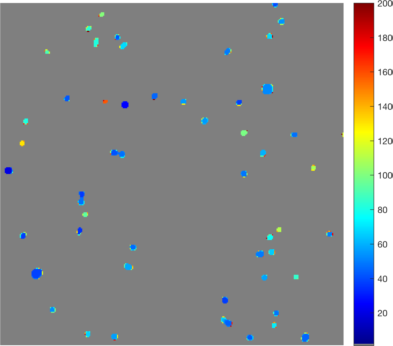

• [ZXSE07] Noha El Zehiry, Steve Xu, Prasanna Sahoo, and Adel Elmaghraby. Graph cut optimization for the Mumford-Shah model. In VIIP ’07 The Seventh IASTED International Conference on Visualization, Imaging and Image Processing, pages 182–187, 2007.